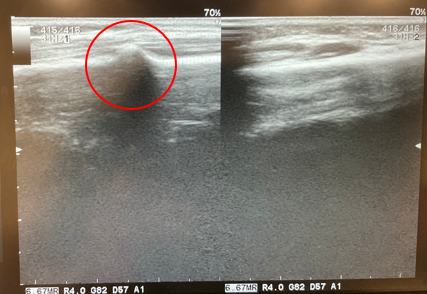

当院では超音波機器で観察が可能/骨折は当院で対応可能です

当院には、超音波観察(エコー)機器があります。 レントゲン検査では分かりにくい細かい骨折の早期発見や、 靭帯や腱、内部出血の状態を詳しく観察することができます。 レントゲンのように放射線被ばくの心配もなく、 その場で迅速な観察が可能です。あまり知られていませんが、骨折は整形外科(病院)だけではなく接骨院でも対応可能です。とくに当院は整形外科にて毎日骨折の対応をしていた院長が対応し、常に整形外科と連携も取っているためご安心ください。固定や治療スケジュールも一人ひとりの状態に合わせて実施していきます。「もしかして…」と思ったら自己判断せずに、 できるだけ早く当院にご相談ください。 早期の適切な判断と治療が、後遺症を残さず、 スムーズな回復への第一歩です。手首の痛みでお困りの方は、どうぞお気軽にご来院ください。